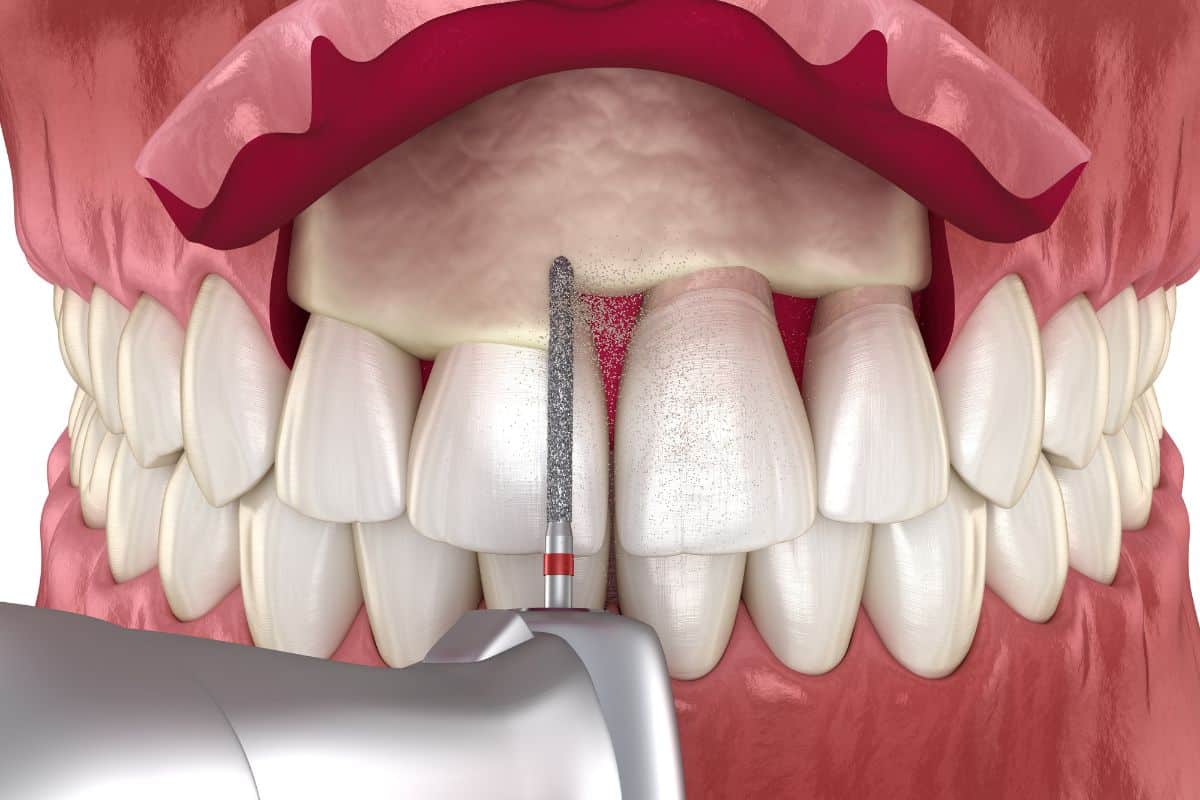

Crown lengthening is a relatively simple procedure that your dentist or oral surgeon can perform. The first step is to numb the area around the tooth or teeth that will be treated. Once you are comfortable, your dentist will make a small incision in the gum tissue and carefully remove any excess tissue. They may also need to remove some bone around the tooth before suturing the gums.

Both functional and cosmetic crown lengthening procedures are completed by removing a small amount of bone and gum tissue from around the tooth. The specific amount of bone and gum tissue that needs to be removed will be determined by your dentist or oral surgeon based on your individual needs. In most cases, the procedure can be completed in one visit to the dentist’s office.

Crown lengthening is a procedure that can be performed for both cosmetic and functional reasons. The procedure involves the removal of gum tissue, bone, or both to expose more of the tooth. It can be done on one tooth, or a group of teeth can be treated at the same time.